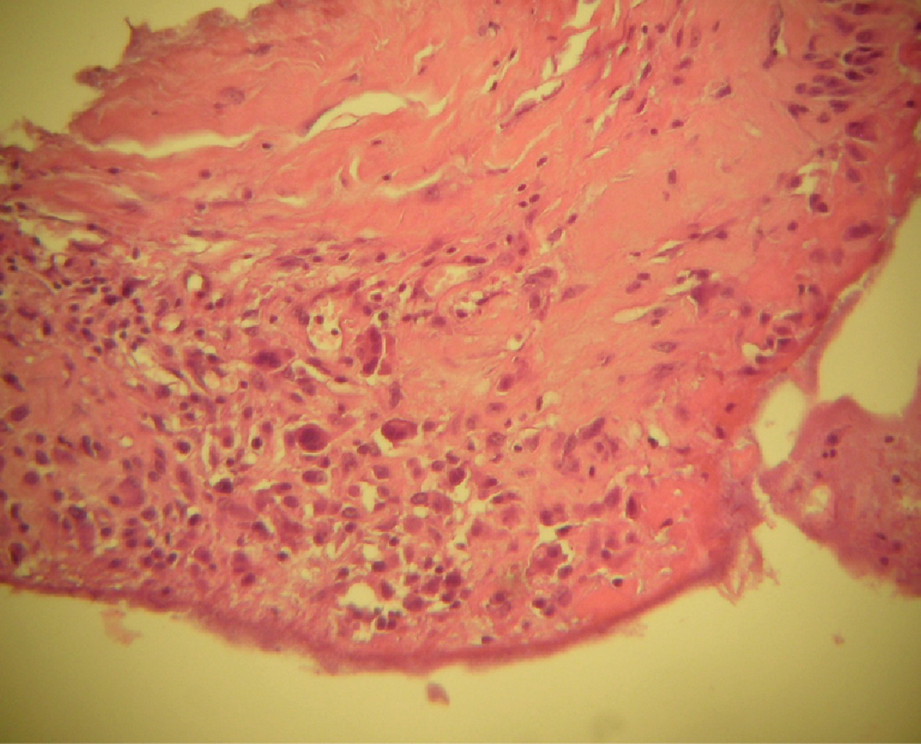

Fig. 16.3

Deposit of fibrinoid material on the inner surface of the capsule (100×)